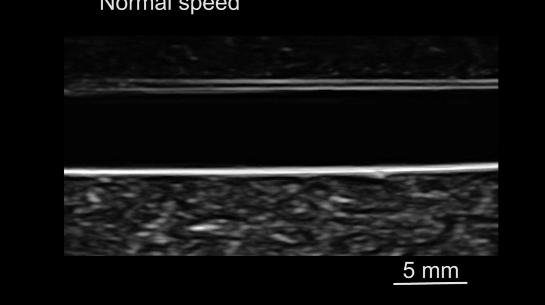

磁驱软体鱼在水中的游动性能

磁驱软体鱼自下而上的游动

为了模拟评估这个“小个子运动员”在“血管”中的游动能力。研究人员们在直径4.1 mm的玻璃管中对其进行了游泳能力测试:

小型机器人在血管中的运动

实验结果显示,当磁场的振荡角设置为20°时,磁驱软体鱼游动速度可以达到最快。但是由于在密闭空间内的碰撞,动能的损失使得游泳速度下降,但最大游泳速度仍可以达到17 cm/s。

磁驱软体鱼在细管中的游动性能